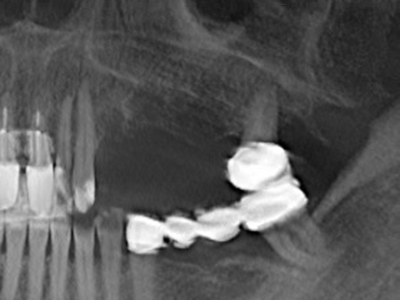

Die Präparation des lateralen Fensters bei der externen Sinusbodenelevation stellt gerade für chirurgisch unerfahrene Implantologen eine große Herausforderung dar. Die knöcherne Bedeckung der Kieferhöhle ohne eine Verletzung der darunterliegenden Schneider’schen Membran abzutragen ist dabei nur ein Teil der Operation – nach Schaffung eines ausreichenden Zugangs muss die Kieferhöhlenschleimhaut vorsichtig mobilisiert werden, um Raum für das einzubringende Material bzw. die Implantate zu schaffen. In dieser Indikation ist die Piezochirurgie zweierlei hilfreich: zum einen kann durch Verwendung diamantierter Instrumente eine selektive Knochenabtragung erfolgen und die darunter liegende Schleimhaut bleibt bei vorsichtiger Vorgehensweise intakt. Zum anderen unterstützen die Ultraschallfrequenzen zusätzlich eine komplikationslose Ablösung der Schleimhaut – sie werden durch spezielle stumpfe Ansätze in den Spaltraum zwischen Schleimhaut und Kieferhöhlenboden übertragen (Cassetta, Ricci et al. 2012, Pereira, Gealh et al. 2014) (Rickert, Vissink et al. 2013). So erscheint es nicht verwunderlich, dass in aktuellen Übersichtsarbeiten über die externe Sinusbodenelevation neben der Verwendung von rauen Implantatoberflächen und dem Einsatz von Knochenersatzmaterialien auch der Einsatz von piezoelektronischen Geräten als positiv bewertet wird (Wallace, Tarnow et al. 2012).

Sollen chirurgische Eingriffe mit unmittelbarer Knochenbeziehung an empfindlichen Strukturen wie Blutgefäßen oder Nerven erfolgen, so bergen rotierende Instrumente ein erhebliches Potential an iatrogener Schädigung. Gerade bei Nervdarstellungen nach iatrogener Schädigung, oder aber im Zuge einer Nervlateralisation für resektive und rekonstruktive Eingriffe oder Implantatinsertionen können piezoelektronische Geräte hilfreich sein Knochendeckel zu präparieren und nervnahe Hartgewebsanteile zu entfernen (Abb. 17-20). Ein leichter Kontakt des Nervstrangs zur Piezospitze bleibt dabei in der Regel folgenlos – allerdings kann eine unvorsichtige Vorgehensweise mit sägeartigen Bewegungen bzw. Ansätzen bei noch vorhandener knöcherner Unterlage durchaus temporäre oder aber auch permanente Nervschädigungen verursachen. Das Risiko einer solchen Schädigung wird jedoch als wesentliche geringer eingeschätzt als unter Anwendung von Säge- oder Fräsinstrumenten (Pereira, Gealh et al. 2014).